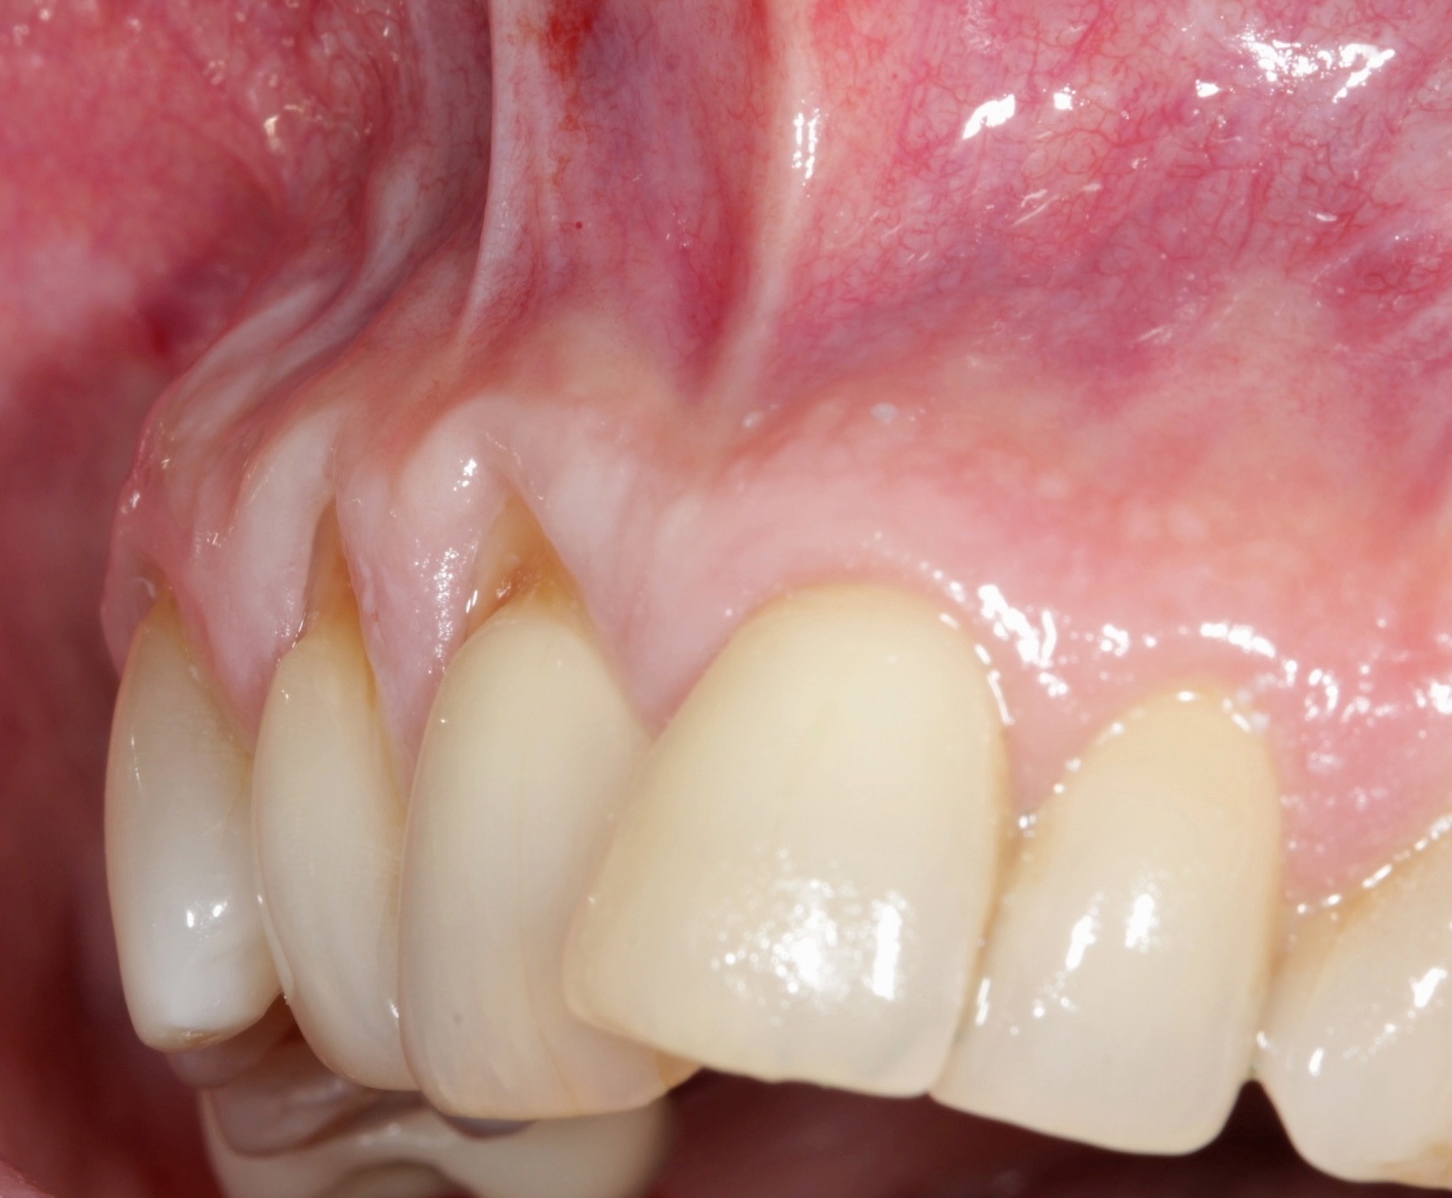

Fig 5. Preoperative. Class 2 Miller trauma-induced recession and associated tooth malposition.

Figure 5